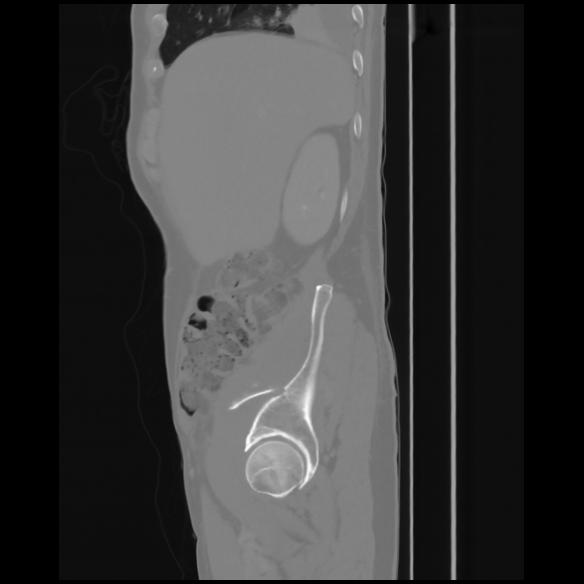

7 CUERPO,CE,Sagittal,3.000,CUERPO,Sagittal,